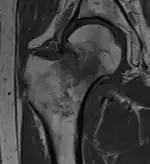

Intertrochanteric hip fracture in a 17-year-old male

Typically, radiographs are taken of the hip from the front (AP view), and side (lateral view). Frog leg views are to be avoided, as they may cause severe pain and further displace the fracture.[5] In situations where a hip fracture is suspected but not obvious on x-ray, an MRI is the next test of choice. If an MRI is not available or the patient can not be placed into the scanner a CT may be used as a substitute. MRI sensitivity for radiographically occult fracture is greater than CT. Bone scan is another useful alternative however substantial drawbacks include decreased sensitivity, early false negative results and decreased conspicuity of findings due to age-related metabolic changes in the elderly.[16]

A case demonstrating a possible order of imaging in initially subtle findings: